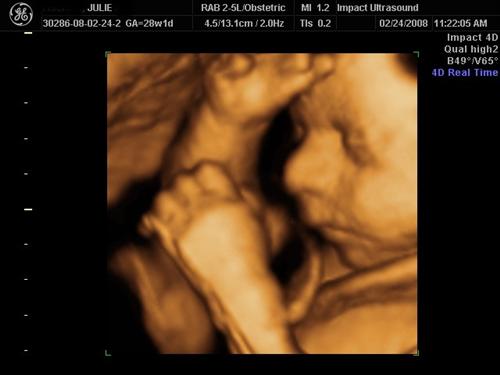

Can see his boy parts between the legs

And I made them confirm the sex: Side view of scrotum & penis... the tech called it a turtle